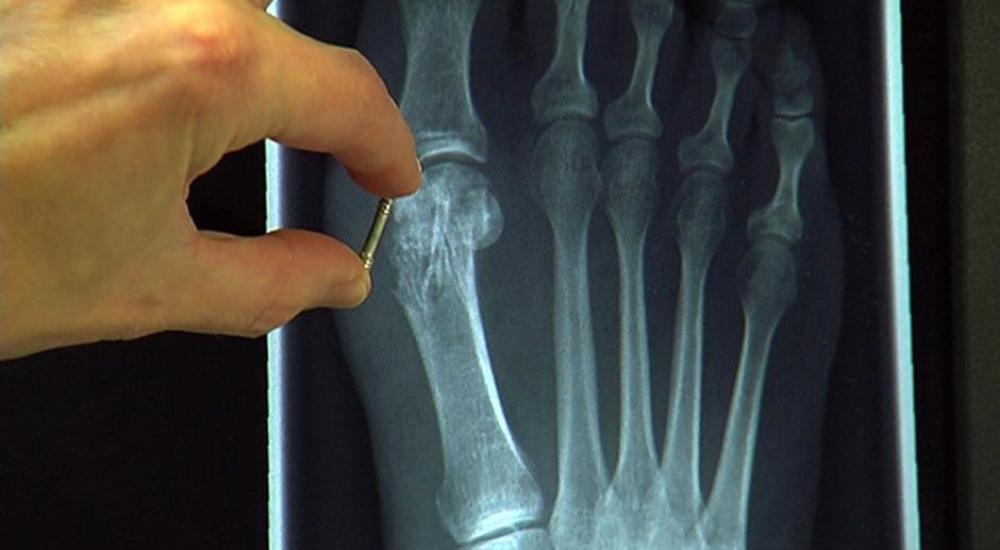

لكن الآن، وبفضل البرغي العظمي، أصبح من الممكن تقليص هذه المعاناة. على الظاهر، يصعب تمييز البرغي العظمي عن البرغي العادي، فهو مدور وطوله ثلاثة سنتيمترات، إلا أن سره يكمن في كونه مصنوع من سبيكة من المغنيسيوم تتحول إلى نسيج عظمي يذوب في الجسم خلال عام ونصف، حسبما تشرح شتوِكتنبورغ كولزمان، أخصائية الجراحة العظمية في ألمانيا، مضيفة بالقول: "يساعد هذا النوع الحديث من البراغي على استقرار العظام جيداً، ما يتيح التئامها جيداً".

ولا يقتصر استعمال البرغي في علاج الكسور فحسب، إذ من الممكن استخدامها أيضاً في تقويم العظام، فكثيراً ما يستخدم في علاج إنحراف إبهام القدم.